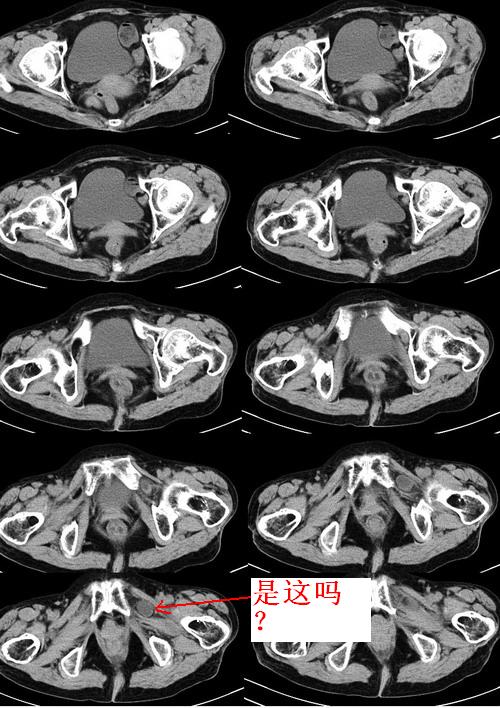

患者女性75岁,腹痛9h余,左腹股沟区可触及一包块,境界不清,压之疼痛明显。

左侧腹股沟股疝。

考虑左侧闭孔疝。

腹股沟疝分直疝和斜疝两种;我认为;是直疝。